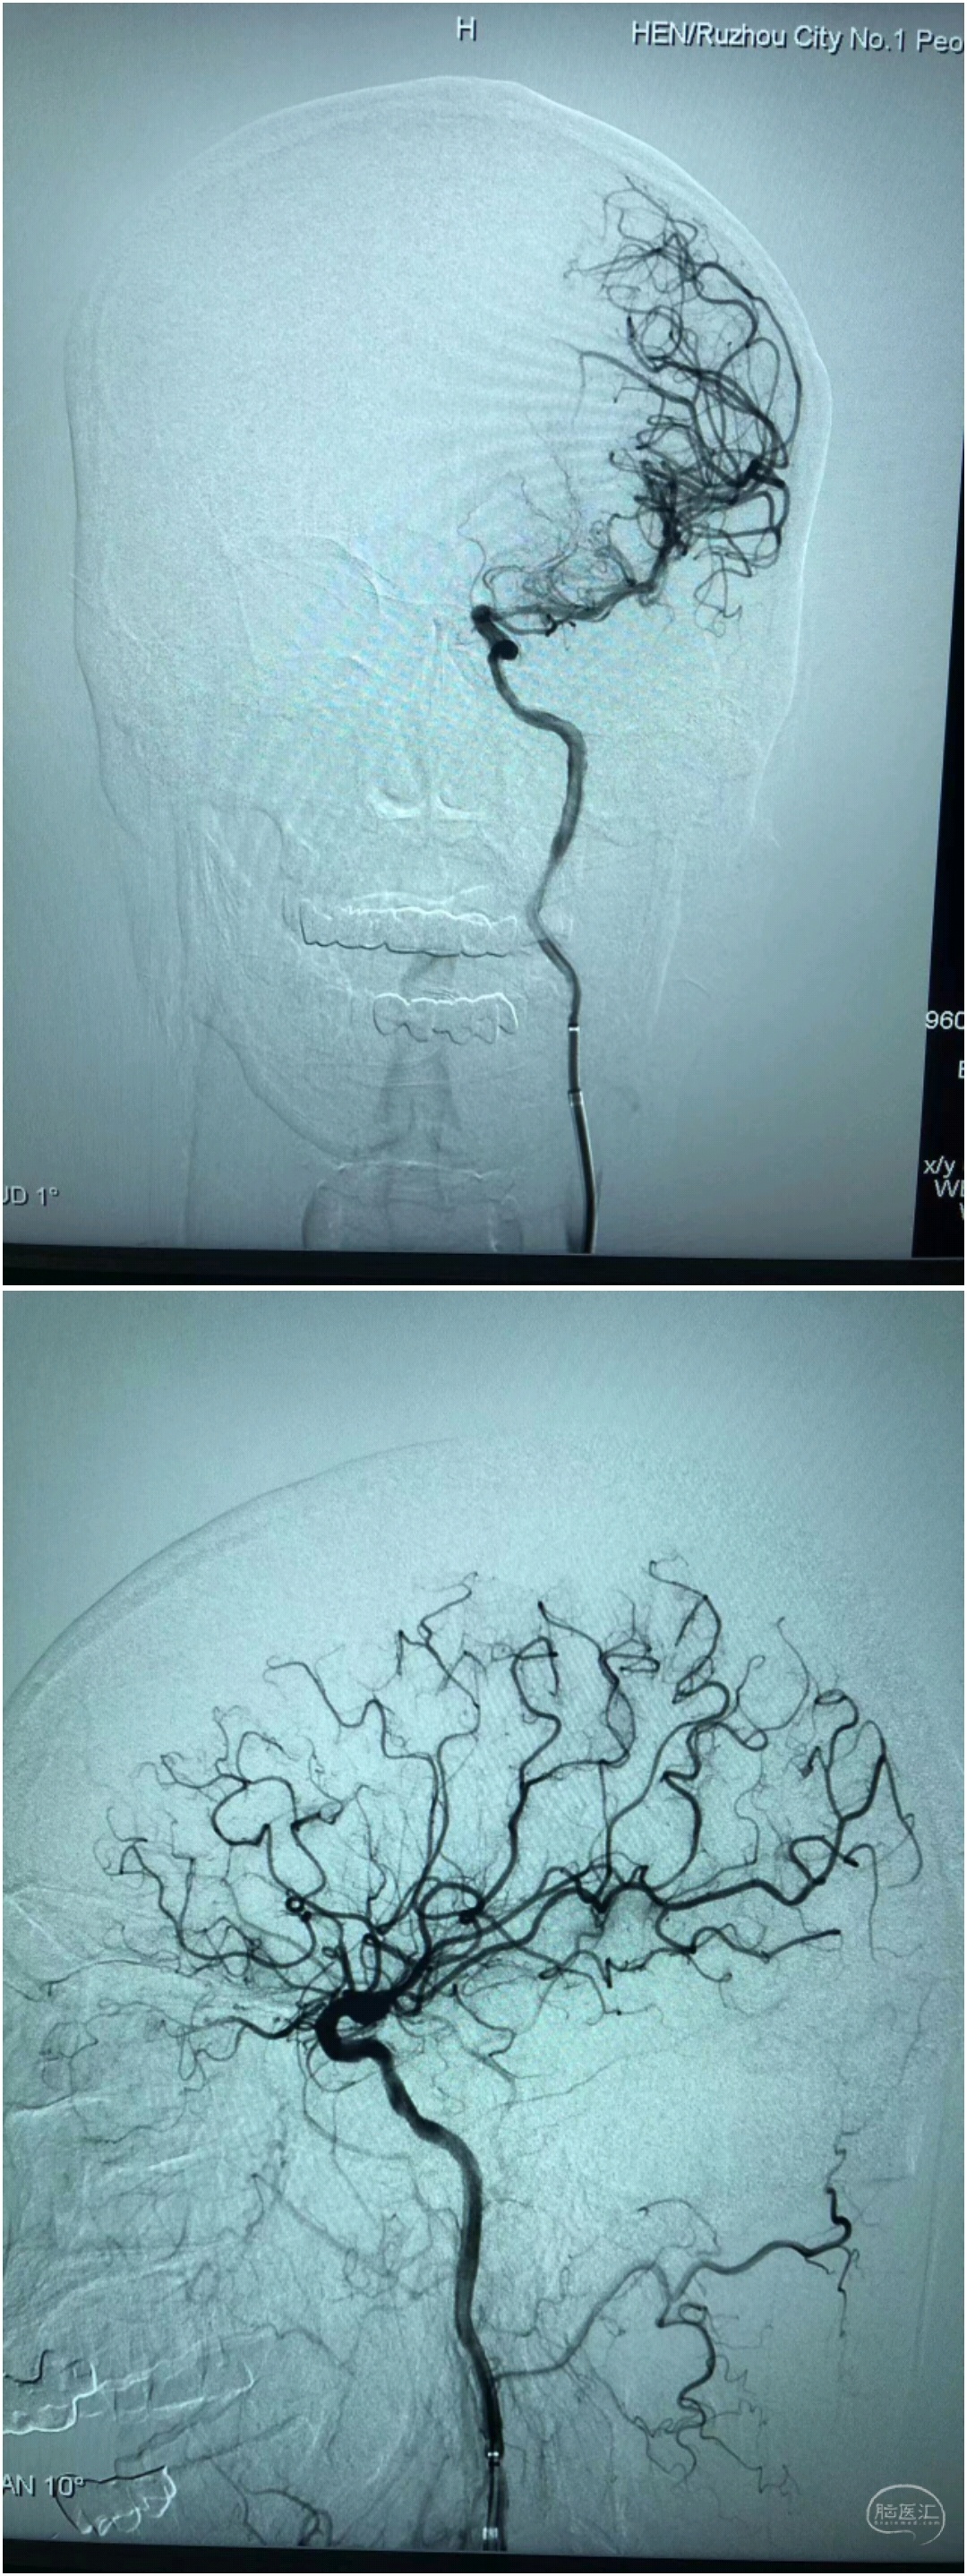

造影:左侧大脑中动脉闭塞,左侧椎动脉闭塞。

Synchro200mm微导丝配合Rebar18微导管穿越闭塞段,经Navien及微导管造影提示闭塞段位于左侧大脑中动脉中段,闭塞段很短,推测血栓负荷量极少。

送入300mmSynchro微导丝,Gateway2.5*9mm球囊扩张后,观察血流,出现弹性回缩。再次扩张后,撤出球囊,交换PLUS导管,送入Enterprise4.0*23mm支架,顺利释放,血流维持可,轻度残余狭窄。

术后造影,血流通畅,TICI分级3级。